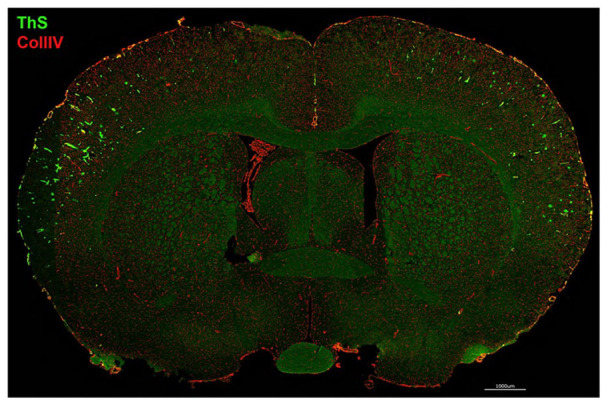

脑淀粉样血管病(CAA)是一种常见的老年性疾病,也是阿尔茨海默病的主要并发症,会导致血管性认知障碍和痴呆。此前,我们生成了一种新型转基因大鼠模型(rTg-D),它能在大脑中产生人类家族性 CAA Dutch E22Q 突变的淀粉样β蛋白(Aβ),并发展成动脉 CAA 2 型。在这里,我们发现纤维状 Aβ 的沉积促进了动脉平滑肌细胞的损失和脑微小出血,这些都可以通过磁共振成像检测到,并通过组织病理学证实。老年 rTg-D 大鼠也会出现认知障碍。脑蛋白质组分析显示,与野生型大鼠相比,患有 CAA 的 rTg-D 大鼠有 241 种蛋白质显著升高,升高幅度大于 50%。rTg-D大鼠中显著降低的蛋白质较少。值得注意的是,与转化生长因子β1(TGF-β1)信号传导有关的蛋白酶--高温要求肽酶 A(HTRA1)升高,并发现它在淀粉样沉积的脑血管中聚集。通路分析表明 TGF-β1 通路升高,并且在 rTg-D 大鼠中检测到 TGF-β1 水平升高。总之,本研究结果为 CAA 的发病机制提供了新的分子见解,并提示了 HTRA1 和 TGF-β1 在疾病过程中的相互作用。